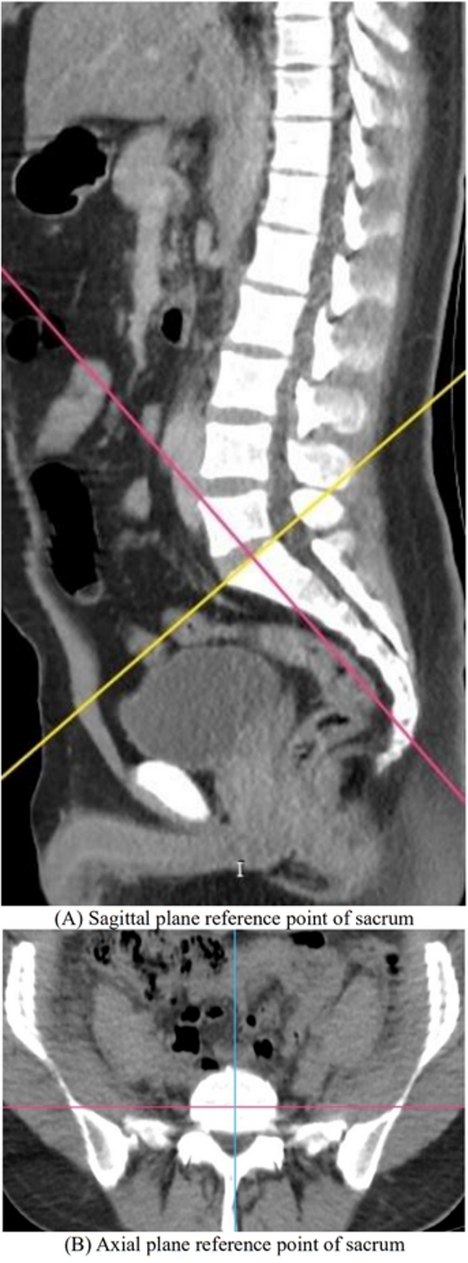

Sex estimation from sacral anatomy in Turkish adults: a machine learning–based analysis

The estimation of sex is the first and foremost step in developing a reliable biological identity during the examination o...